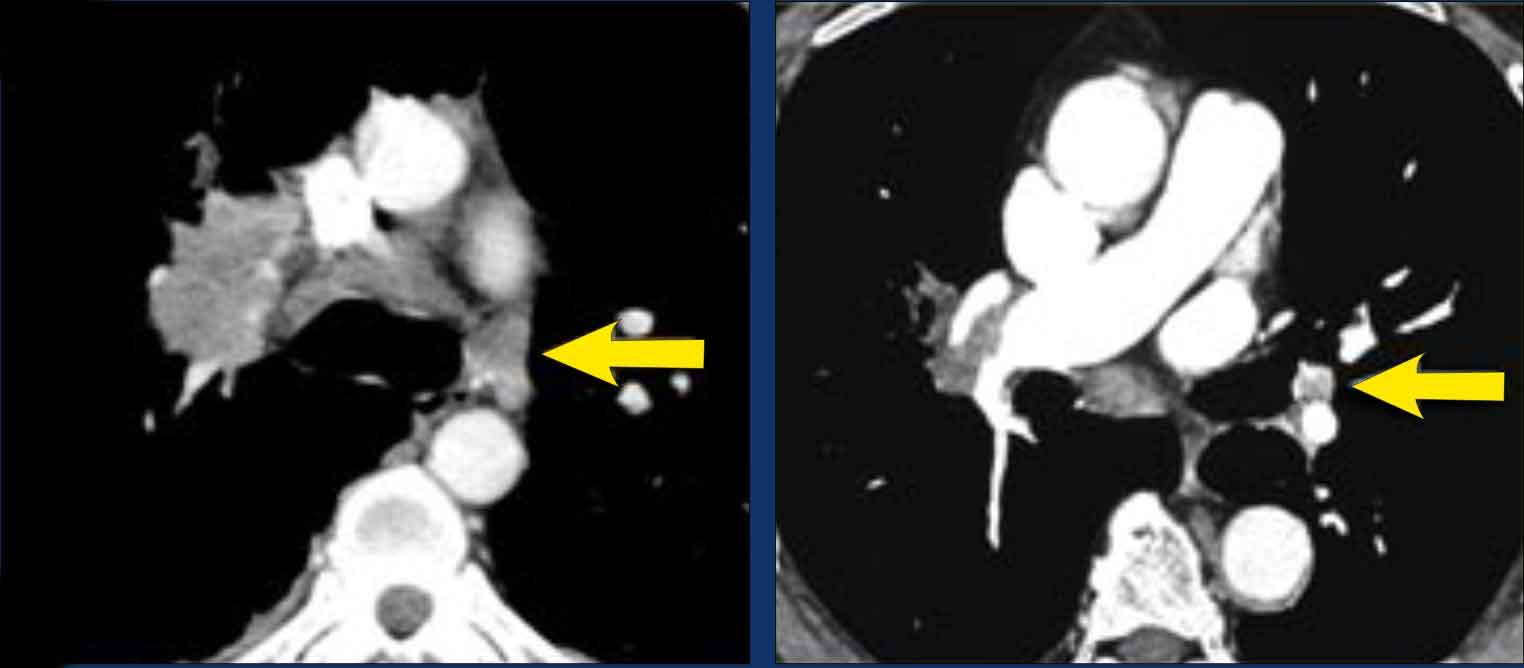

Phân giai đoạn M

Phân giai đoạn M dựa trên sự hiện diện của các di căn, vị trí và tính đa ổ của chúng.

M0 là không có di căn và M1 có nghĩa là di căn xa.

Cần phân biệt giữa bệnh di căn tại vùng hoặc trong lồng ngực (M1a) và bệnh di căn xa, có thể là đơn độc (M1b) hoặc đa ổ (M1c), trong một hệ cơ quan đơn lẻ (M1c1) hoặc trong nhiều cơ quan (M1c2).

Hình minh họa

M1a: Bệnh di căn tại vùng (hoặc trong lồng ngực) được định nghĩa là tràn dịch màng phổi hoặc màng ngoài tim ác tính hoặc các nốt, cũng như các nốt phổi riêng biệt ở phía đối bên.

M1b là một tổn thương di căn ngoài lồng ngực đơn độc trong một hệ cơ quan đơn lẻ. Cần nhấn mạnh rằng, một hệ cơ quan bao gồm tất cả các vị trí của hệ cơ quan đó phân bố khắp cơ thể, hoặc cả hai bên trong trường hợp cơ quan đôi.

Điều này có nghĩa là nhiều tổn thương ở các vị trí khác nhau của hệ xương hoặc da là bệnh M1c1.

Tuy nhiên,

nhiều tổn thương ở cả hệ xương và tuyến thượng thận là bệnh M1c2.

M1b: Di căn ngoài lồng ngực đơn độc trong một hệ cơ quan đơn lẻ.

Có thể là ở một hạch bạch huyết ngoài vùng (không kèm di căn gan) hoặc một tổn thương di căn đơn độc ở gan (không kèm hạch bạch huyết ngoài vùng).